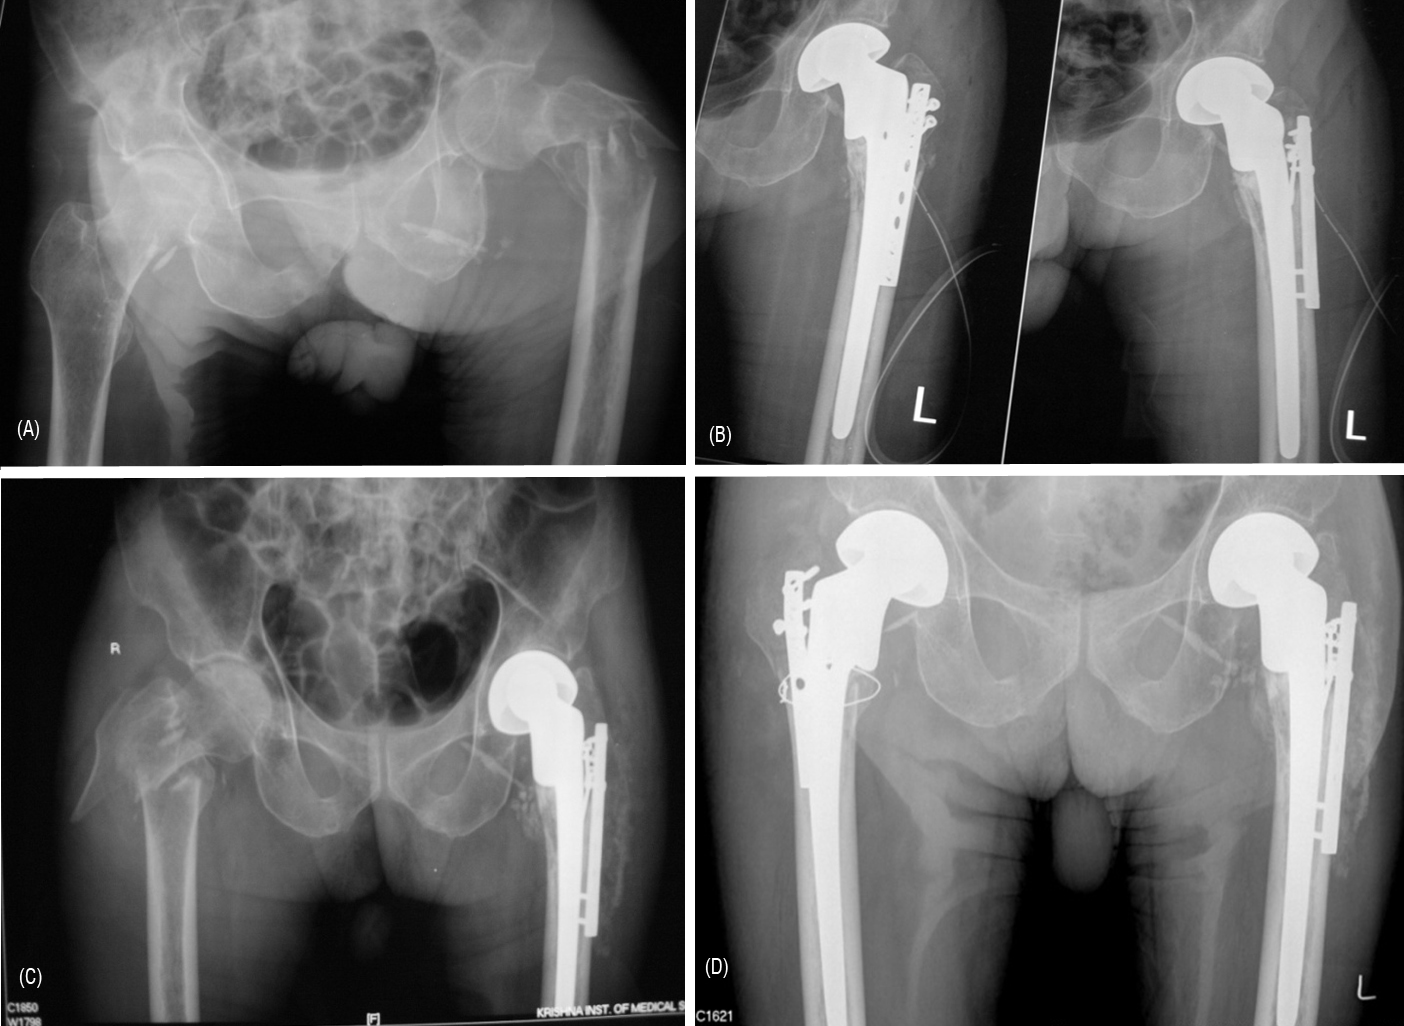

Total hip replacement is not advisable for IT fractures as a primary procedure, due to high risk of dislocation. Total hip replacement may be the only option for certain complications following internal fixations for intertrochanteric fractures. In such rare instances, when THR is under taken, one may have to use large heads, constrained liners, long stems with calcar replacement (Figures 7A, 7B, 7C, 7D).

Figure 7: (A) comminuted IT fracture of the left femur, (B) Postoperative radiograph, (C) Similar IT fracture of right femur 4 months later, (D) Similar reconstruction postoperative radiograph.